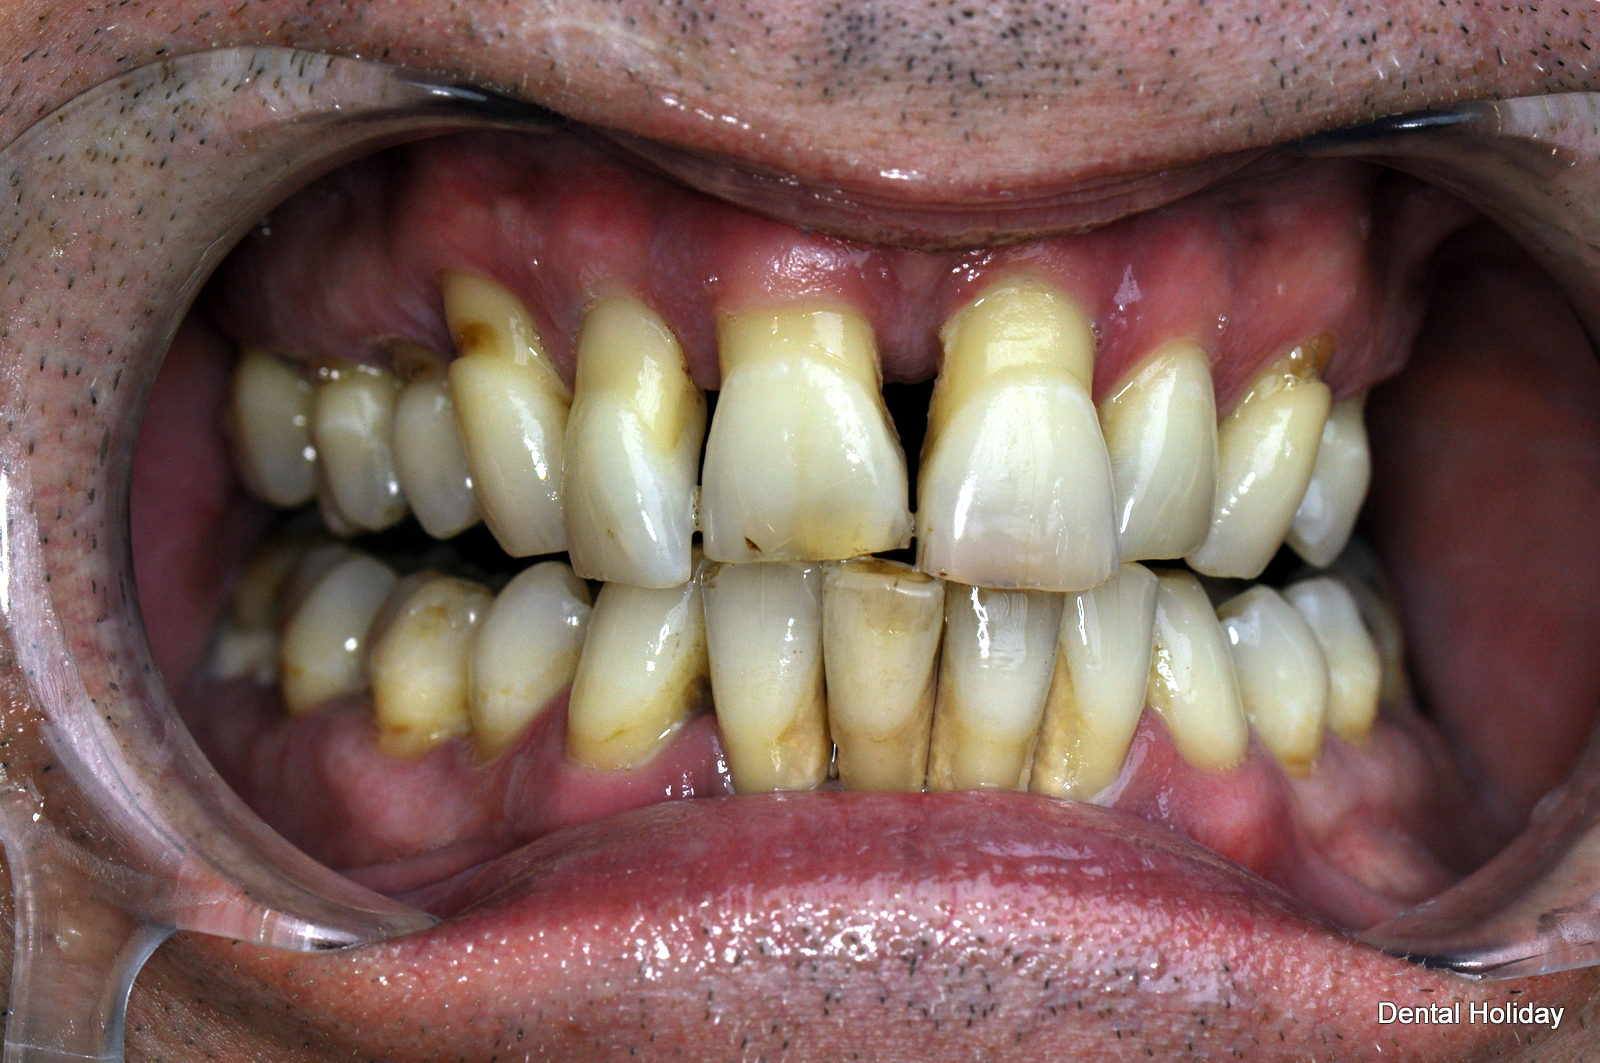

He started his dental treatment with us just before Christmas 2015 and by April 2016 his full mouth reconstruction of the upper and lower teeth was successfully completed.

As you can see on the x-ray here, this included 14 implants and 28 crowns in total, as unfortunately most of his teeth were loose. As you can see from the photographs, the final results provided a fixed, balanced smile, with no worry of ever having to wear a dreaded denture.